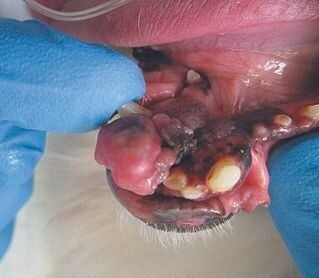

11才のとき、トリミング時に行う歯のチェックの際、口の中に見つかった腫瘍